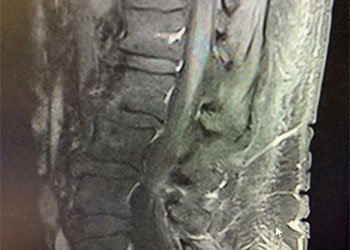

Spine:

Thoracic Spinal Cord Tumor Case Presentation

Author: Xavier P. J. Gaudin D.O., F.A.C.O.S., Read More!